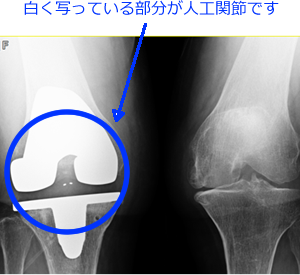

変形性膝関節症や関節リウマチなどにより変形した関節をセラミック、ポリエチレンなどでできた人工膝関節で入れ替えることで痛みがなくなります。

患者さんの年齢や骨の形状、質によって骨セメントを用いる場合とセメントを使用せずに直接骨に固定する場合とがあります。

図2:手術後 |